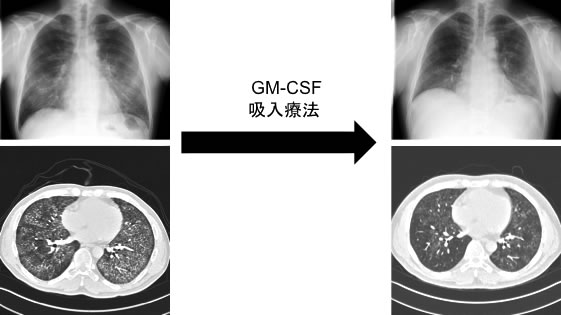

肺胞蛋白症に対するGM-CSF吸入療法(図14)や、LAMに対するmTOR阻害薬を用いた治療など、新しい治療にも積極的に取り組んでいます。

図14. 自己免疫性肺胞蛋白症に対するGM-CSF吸入療法

重症の自己免疫性肺胞蛋白症に対しては、一般的には人工心肺と全身麻酔併用下に全肺洗浄療法を行いますが、負担の大きい治療です。この症例ではGM-CSF吸入療法のみで肺胞内蛋白蓄積が軽快し、在宅酸素療法から離脱できました。